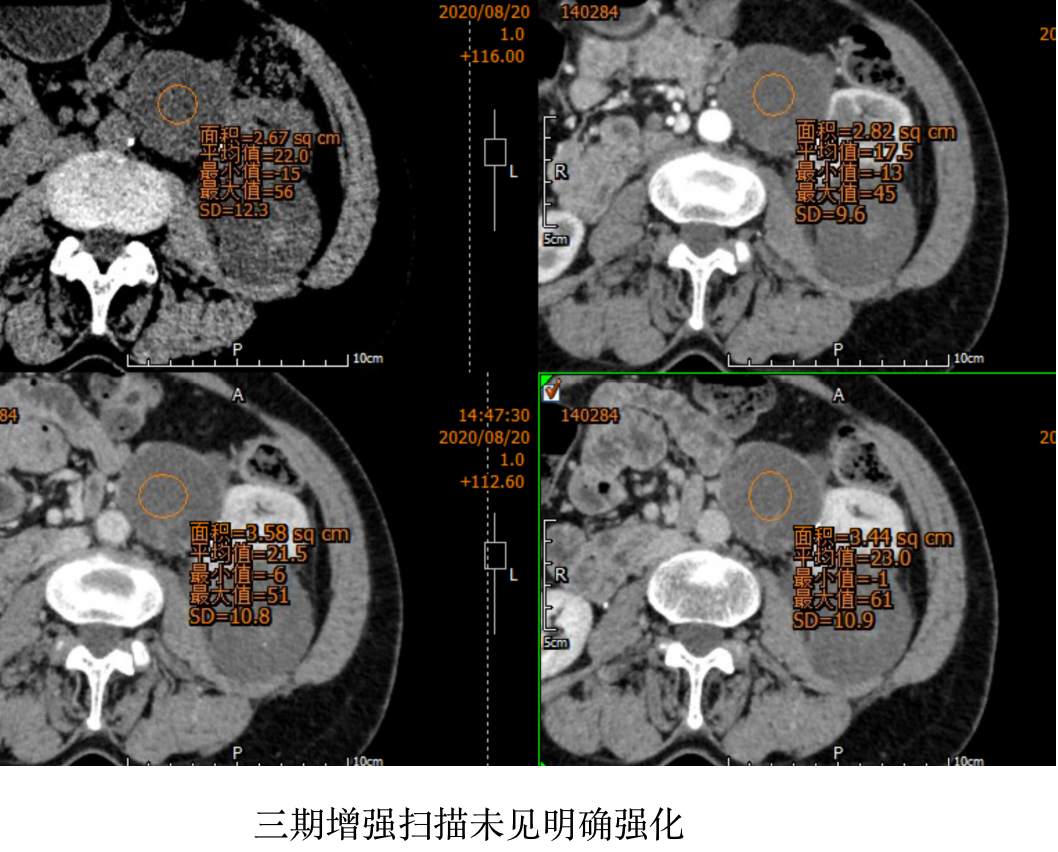

CT值: